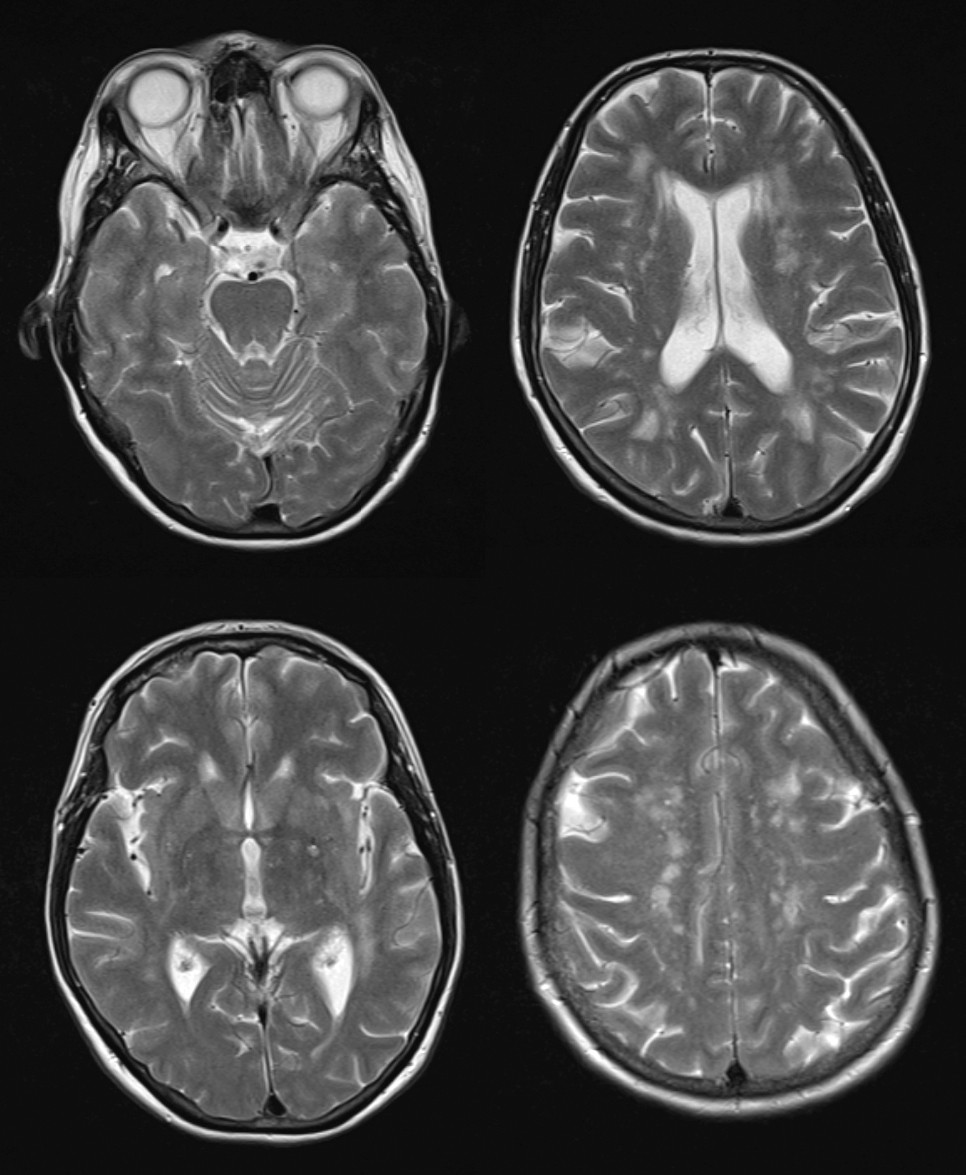

Flere populasjonsbaserte studier med MR-undersøkelser har vist forhøyet forekomst av subkliniske infarkter hos personer med migrene, spesielt migrene med aura (17). I enkelte studier har man også funnet en forhøyet forekomst av uspesifikke hvitsubstanslesjoner i hjernen, mens andre ikke har gjenfunnet dette (18, 19) (fig 2). Man har imidlertid ikke kunnet påvise noen sammenheng mellom slike tilfeldig oppdagede radiologiske endringer og redusert kognitiv funksjon hos personer med migrene, og den kliniske betydningen av slike funn er usikker (20).